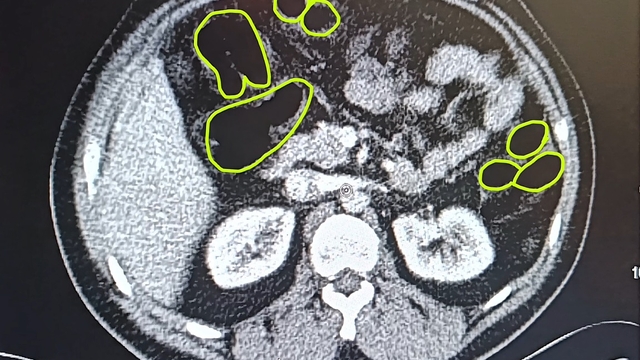

İl Jandarma Komutanlığı ekipleri, İran uyruklu A.O. (51), M.S. (37) ve P.S..'nin (28) ülkelerinden kente uyuşturucu getireceği bilgisine ulaştı. Şüpheliler Kocasinan ilçesi Himmetdede Mahallesi'nde taksi ile kente girmek istediği sırada durduruldu. Araçta yapılan aramada 15 gram esrar, 5 gram bonzai ve 117 adet uyuşturucu hap ele geçirildi. Gözaltına alınan 3 şüpheli muayene olmak üzere Kayseri Şehir Hastanesi'ne getirildi. Röntgen ve ultrason sonrası kontrollerde 3 şüphelinin midesinde uyuşturucu madde olduğu belirlendi. Şüphelilerin yuttukları uyuşturucuları kente sokmaya çalıştıkları tespit edildi. Kapsüller, sağlık ekibinin müdahalesiyle çıkarıldı. Taburcu edilen şüpheliler, İlçe Jandarma Komutanlığı'na götürüldü.